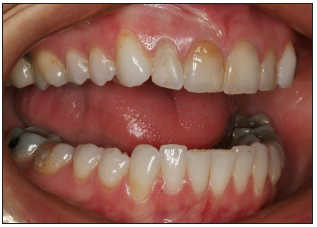

Right and left full smile views

Use retractors to pull back the lips to show the pre-molars, and molars when possible.

The vertical midline of the image should be the lateral incisor. The horizontal midline is the incisal plane, perpendicular to the vertical midline.

Focus camera on lateral incisor. Proper depth of field will allow other visible teeth to be in focus.

Natural asymmetry should be produced.